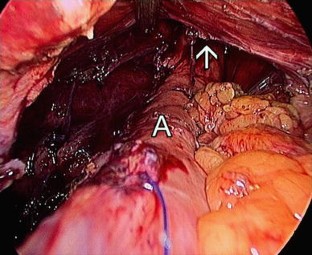

Fig. 1